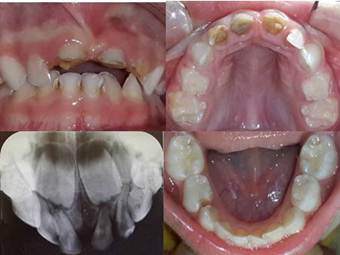

A los 30 días se cementaron de manera definitiva las coronas de cerómero ADORO Ivoclard/Vivadent con Relyx U200 de 3M ESPE. La integridad coronaria en el sector anteroinferior se restituyó con resinas compuestas, y el sector posterior se rehabilitó con coronas de acero elaboradas en laboratorio. Con el objetivo de controlar los procesos de desmineralización – remineralización, se realizó una topicación con fluoruros de alta concentración Clinpro TM White Varnish de 3M ESPE, recitando a la paciente para sus controles clínicos – radiográficos a 1 mes (Figura 3.), 6 meses, 1 año (Figuras 4. A y A´), 2 años del alta integral (Figuras 4. B y B´).

Figura 4 A – A´: Control clínico – radiográfico: 12 meses

Figura 4 B: Control radiográfico: 26 meses.

Figura 4 B´: Control clínico: 30 meses.